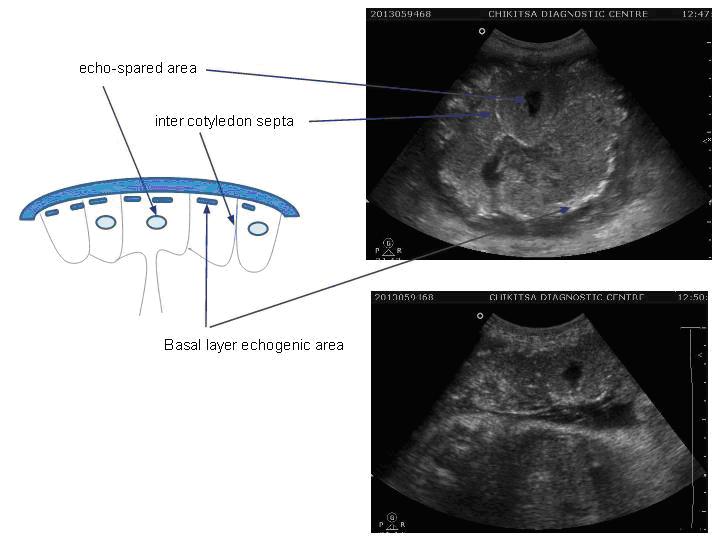

Grade - 3

Is the late phase represents the mature placenta

Chorionic plate - Plate appears interrupted by indentations, which now extend to the basal layer and probably represent the inter cotyledon septa.

Placental substance - Placenta divided into compartments which presumably demarcate the cotyledons. The central portion of these compartments shows echo-spared or fallout areas.

Basal layer - Echogenic densities persist and become larger and denser

Chorionic plate indentation that extend all the way to the basal layer